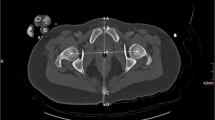

Marker placement was performed following the instructions for use. Two types of external calibration markers were attached: (1) DSSM at “belt-buckle” position in front of the pubic symphysis; (2) standard external marker between the patients’ legs (Fig. 1).

All radiographs were stored in a picture archiving and communication system (PACS). Measurements were performed using a proprietary DICOM viewer (IMPAXX EE). The outer circumference of all markers was identified by three points. The diameter was measured in mm with one decimal. Repeated measurements of all radiographs were performed by one experienced observer. If two results differed, a third measurement was performed. The mean of the two best fits was used. The following markers were measured in the same order in all radiographs: (1) DSSM, (2) ICM (femoral head component and acetabular component; the best visible marker was marked and used for the analysis), and (3) the ECM.

In the present study, post-operative radiographs of patients with unilateral THA were performed with two types of external calibration markers: (1) anterior marker at “belt-buckle” position in front of the pubic symphysis, and a (2) standard external marker between the patients’ legs. The internal hip components were used as individual reference.